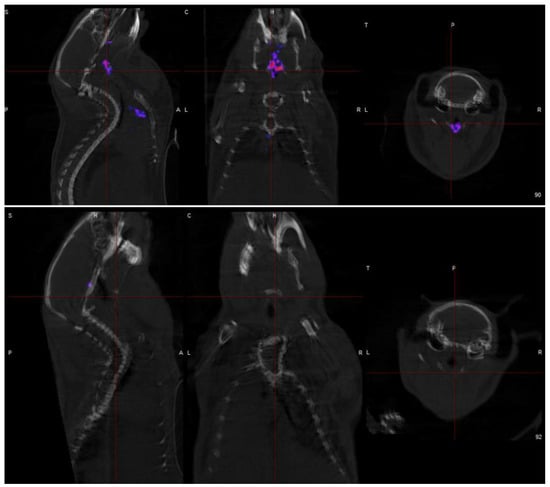

- Early detection of vulnerable coronary plaques because 18F NaF accumulation in micro-calcification before visibility on CT, allowing earlier intervention. Furthermore, 18F NaF uptake can differentiate between active and indolent calcification in coronary arteries, providing crucial information on plaque activity and potential instability.

- Coronary plaque specificity is demonstrated to be exceptional for detecting micro-calcification in coronary atherosclerotic plaques by 18F NaF, a hallmark of vulnerable lesions. This specificity arises from the ability of 18F NaF to reflect the exchange of hydroxyl groups in hydroxyapatite crystals, which is a crucial step in the calcification process of coronary plaques.

- Coronary imaging challenges due to their small size, constant motion, and proximity to the metabolically active myocardium is overcome by 18F NaF to provide:

- Superior coronary visualization because the low myocardial uptake of 18F NaF enables clear visualization of coronary plaques.